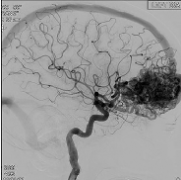

一般来说,AVM位于大脑深处更容易出血。脑动脉瘤,大约20%患有动脉瘤的人都有这种症状动静脉畸形,也会增加出血风险。干预对于较大限度地提高儿童动静脉畸形(AVMs)的疗效至关重要...

脑动静脉畸形(AVMs)由发育不良的血管和直接的动静脉分流组成,可自发出血。在儿童中,较高的终生出血风险需与治疗相关的发病率相平衡。作者描述了一种合作的多模式策略,从而...